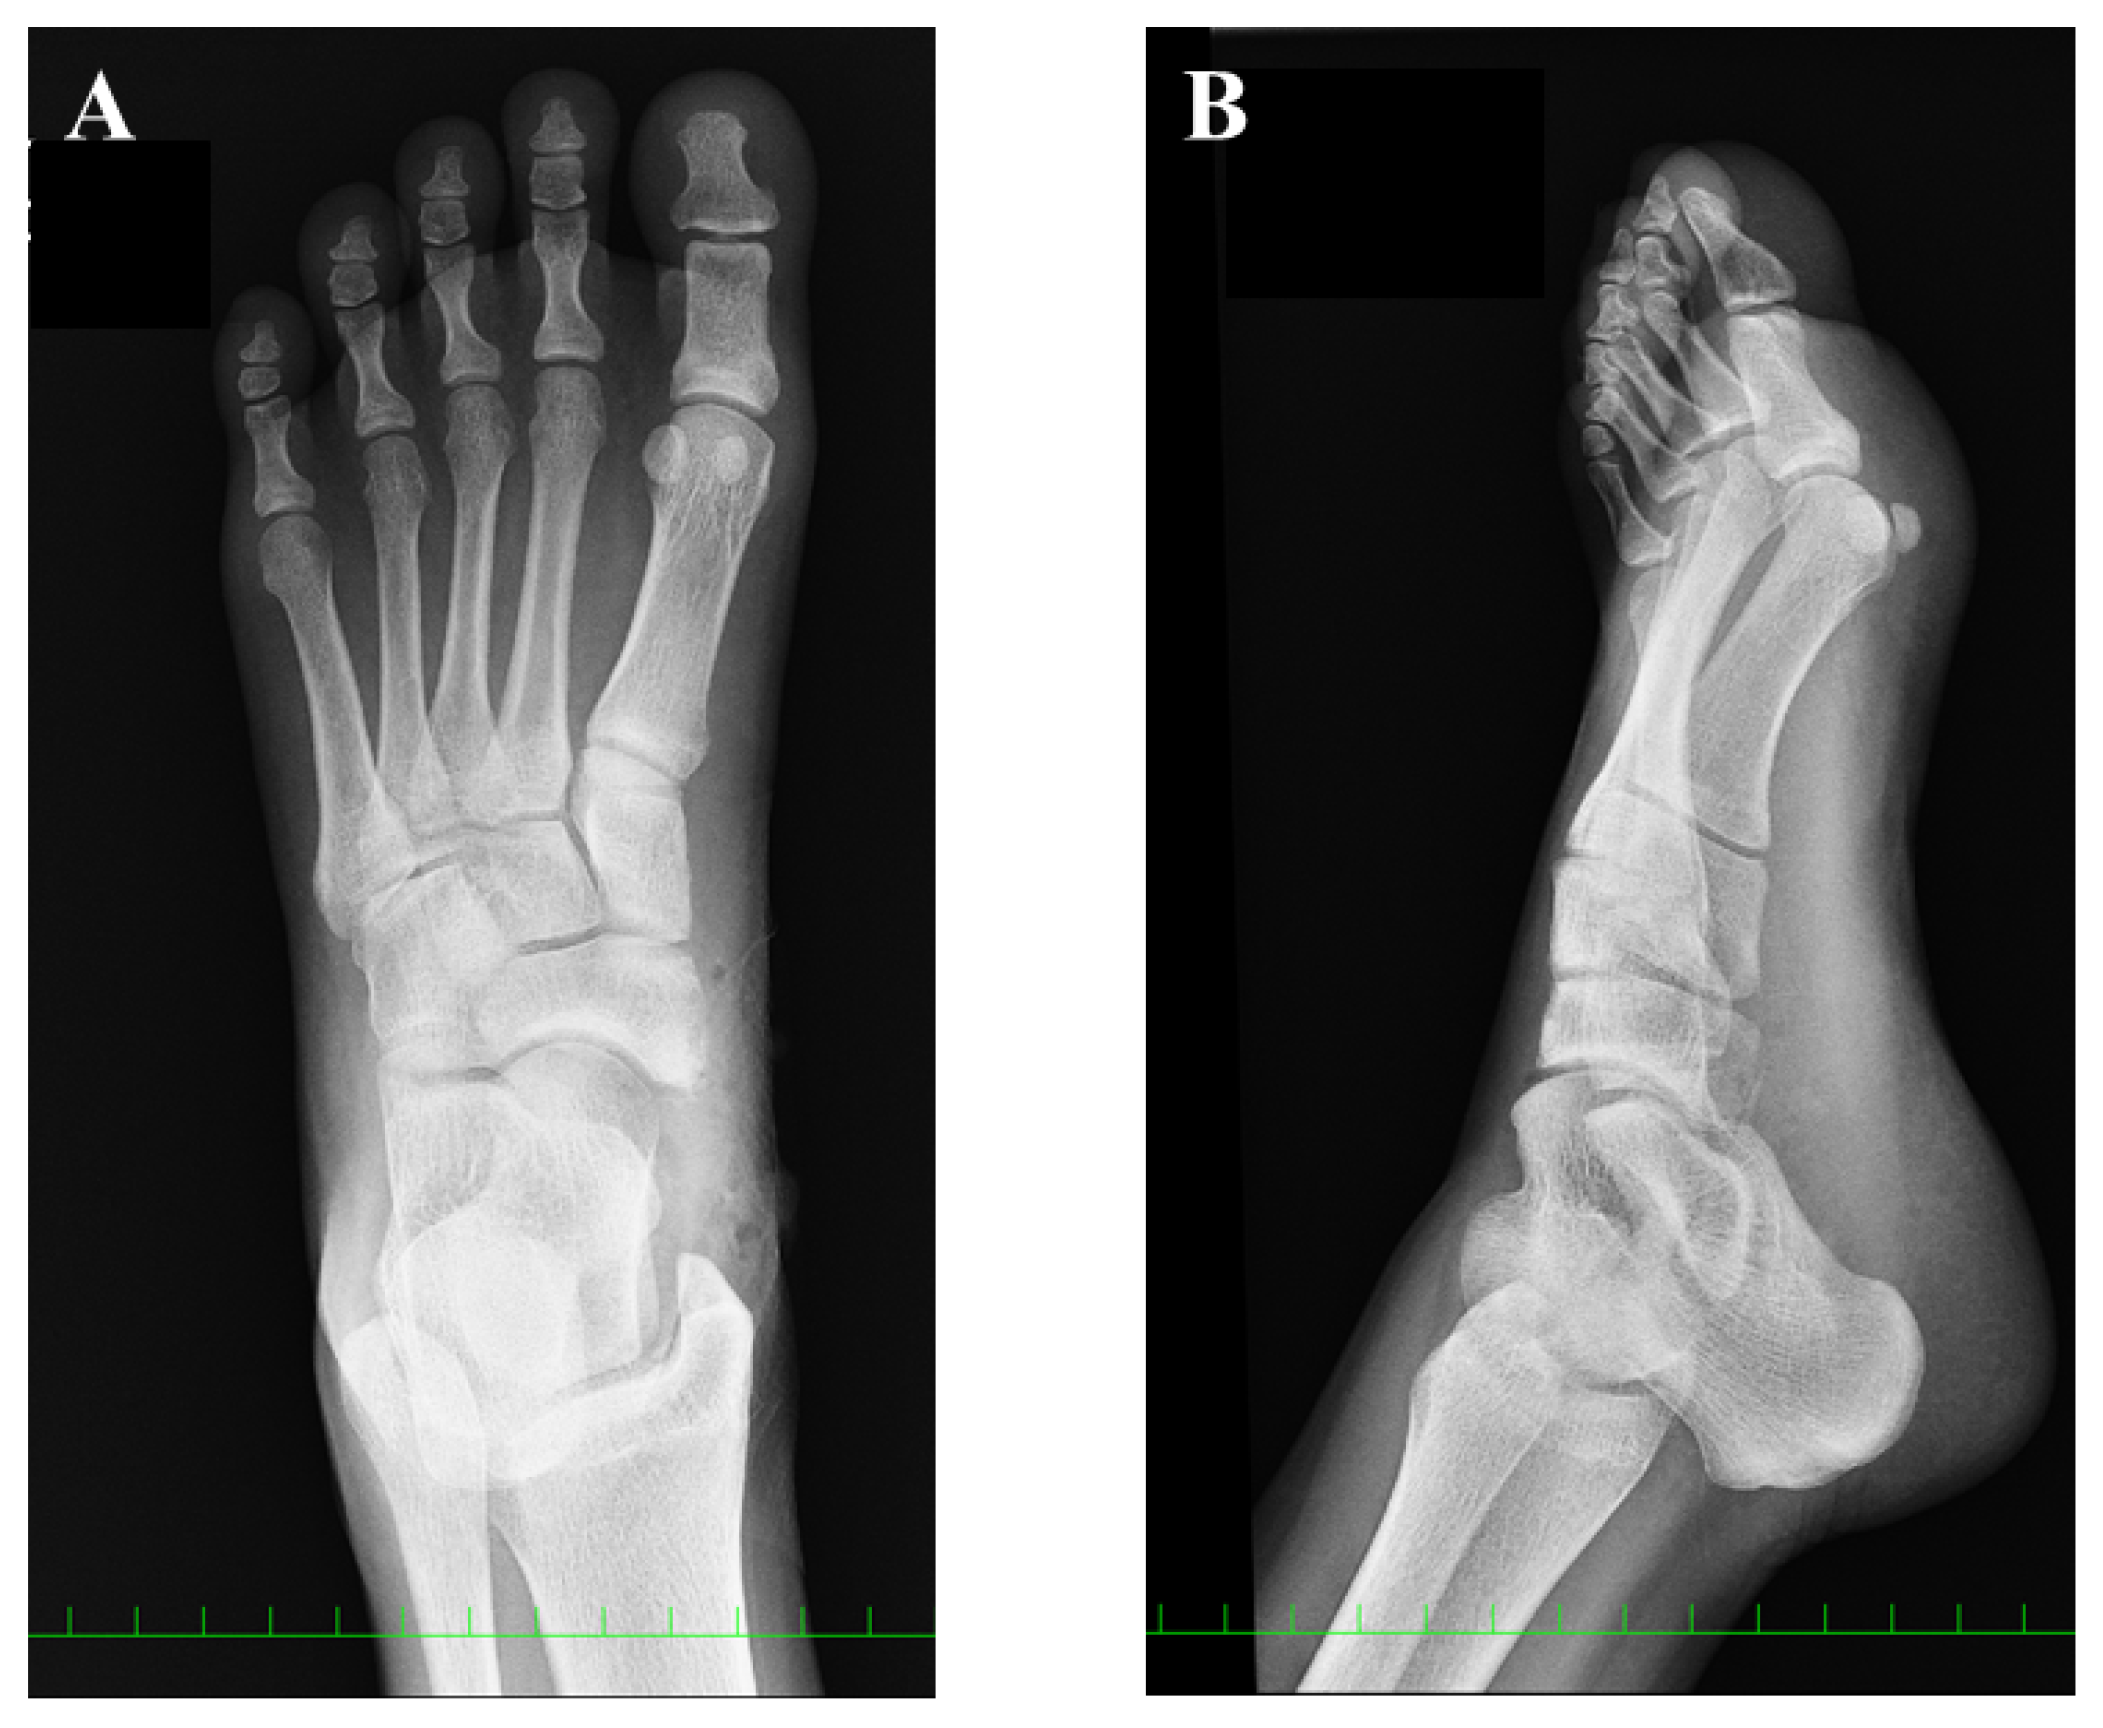

Postoperative plain radiographic findings: (A) anteroposterior view and (B) oblique view.

At the 12-month follow-up examination, the AOFAS score and VAS were 100/100 and 0/10, respectively. The FAOS was as follows: symptoms, 100/100; pain, 100/100; function, daily living, 100/100; function, sports and recreational activities, 95/100; and quality of life, 100/100. Plain radiographs showed union of the bony fragment with the TPT to the navicular body (Figure 6). The CT findings showed the presence of the navicular bone (Figure 7). The patient has played soccer at the same pre-injury level without complaints.

Figure 6.

Plain radiographic findings at 12 months after surgery: (A) anteroposterior view and (B) oblique view. Union of the bony fragment with the tibialis posterior tendon to the navicular body was confirmed (red arrow).